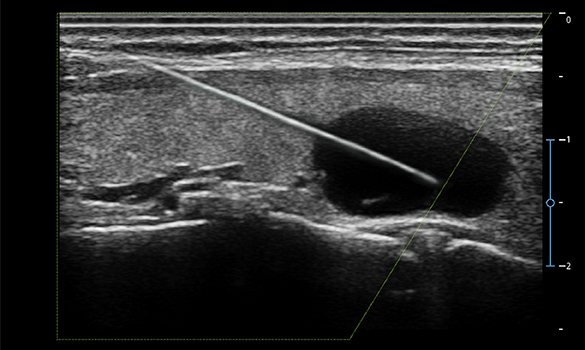

Vis-Needle

Enhances needle visibility in real time to clearly identify needle position during interventional procedures.